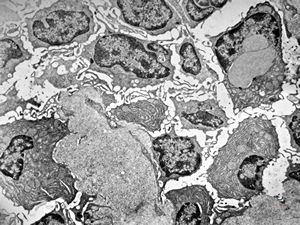

M,39y. | lymph node - metastasis of adenocarcinoma